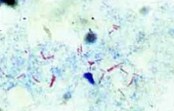

- BAAR: bastonetes delgados, ligeiramente curvos, isolados, aos pares ou em grupos corados em vermelho com o fundo azul.

- Outros microrganismos: corados em azul.